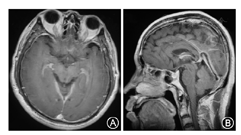

SIH患者2例头MR平扫结果正常,1例患者既往有高血压病史,头MRI显示侧脑室周围脱髓鞘样改变,余未见异常。SIH头MRI异常表现包括:脑叶出血、硬膜下血肿、脑静脉窦血栓、小脑扁桃体下位、蛛网膜下腔出血、脑室变小、垂体充血、脑静脉窦扩张、弥漫性硬脑膜强化。

(1)病例1:女,37岁,因"头痛1个月"入院。表现为后颈枕部钝痛,向肩胛部放射伴恶心、耳鸣,躺下后10 min可缓解。病后第2天头CT正常。病后第3天头MRI正常。查体:四肢腱反射活跃-亢进,余神经系统查体(-)。病后第5天腰椎穿刺,压力35 mmH2O,白细胞10×106/L,蛋白0.74 g/L,糖、氯化物正常。病后1个月头CT:右侧颞、顶、额部硬膜下血肿;小脑幕增宽,考虑硬膜下血肿。病后41 d头MRI平扫+增强:右侧额顶颞叶亚急性晚期硬膜下血肿;左侧颞、顶、枕部、双侧小脑幕上硬膜下少量出血;小脑扁桃体下位;弥漫性硬脑膜强化(图1)。颈胸腰椎增强MRI正常。(2)病例2:男,53岁,因"头痛3 d"入院。表现为前额部胀痛,伴后颈背部疼痛,躺下休息可缓解。神经系统查体(-)。病后3 d时腰穿,压力50 mmH2O,脑脊液白细胞6×106/L,蛋白0.65 g/L,糖、氯化物正常。起病当天头CT正常。发病第7天头MRI平扫+增强:硬脑膜、小脑幕异常增厚强化(图2)。头MRV、颈胸腰椎增强MRI正常。(3)病例3:女,39岁,因"头痛20 d,左侧肢体无力5 d"入院。表现为全头搏动性胀痛,平卧位减轻,坐起后加重,伴头晕、头鸣、耳鸣、颈部僵硬感。发病第4天头CT正常。第13天、18天各出现一次癫痫大发作,持续约1 min。第13天时头MRI正常。第15天突发右侧肢体无力,查体:右上肢肌力4级,右下肢0级,右侧Babinski征、Chaddock征(+),颈抵抗(+)。腰穿测不出压力。第19天复查头CT示左额顶叶高密度影,提示硬膜下血肿。第21天头MRI:硬膜下血肿吸收明显,遗留左侧额叶皮质下片状长T2信号。全脑DSA检查正常。(4)病例4:男,44岁,因"头痛半个月"就诊。头顶及颈部持续胀痛,坐起或站立时明显,平卧位可减轻。发病第4天头CT:未见异常。腰穿压力20 mmH2O,白细胞0,蛋白0.8 g/L,糖、氯化物正常。第22天头MRI增强:脑膜强化、脑室缩小。颈胸腰椎增强MRI正常。(5)病例5:女,28岁,因"头痛4 d"就诊。头痛位于头顶及后颈背部,胀痛,平卧时减轻,站立时加重难以忍受,伴头晕、恶心、呕吐。查体:颈抵抗3横指。腰穿压力30 mmH2O,白细胞6×106/L,蛋白1.3 g/L,糖、氯化物正常。发病第2天头CT正常。半个月时头MRI:垂体饱满。头MRA 、MRV和颈椎MRI正常。

SIH在MRI上主要表现为硬脑膜弥漫性增强、硬膜下积液或出血、垂体增大、静脉窦扩张、脑室变小以及小脑扁桃体向下移位等[3,7]。20%的患者不出现硬脑膜强化或其他任何MRI异常表现[7]。本文中五例典型患者MRI表现涵盖了SIH大部分MRI特点。SIH的头MRI存在动态演变过程,病程初期MRI结果正常,可以在病程中发生变化,本研究中病例1和3患者的头MRI均存在动态演变过程。